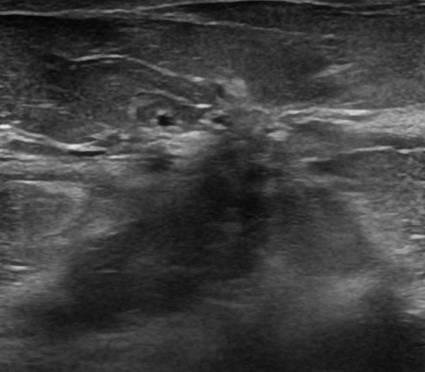

Ung thư vú

» Thông tin: Nữ giới – 50 tuổi.

» Lâm sàng: Khối tuyến vú.